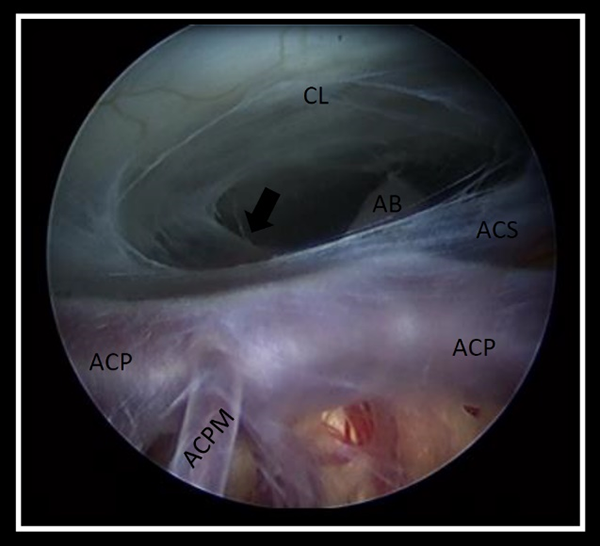

Al realizar el análisis de las grabaciones, la ostomía se consideró satisfactoria si: a) el diámetro permitió el pasaje del endoscopio, y así corroborar la correcta disección de la membrana de Liliequist, objetivando la exposición de la arteria basilar y algunas de sus ramas principales, b) visualización del movimiento ondulante de los bordes libres de la ostomía por el paso del LCR (Figura 1).

Figura 1. Imagen endoscópica obtenida desde la ostomía que permite observar la disección correcta de la membrana de Liliequist (flecha), objetivando la exposición completa de la arteria basilar y sus ramas principales. AB: arteria basilar, ACS: arteria cerebelosa superior, ACP: arteria cerebral posterior, ACPM: arteria central posteromedial izquierda CL: clivus.